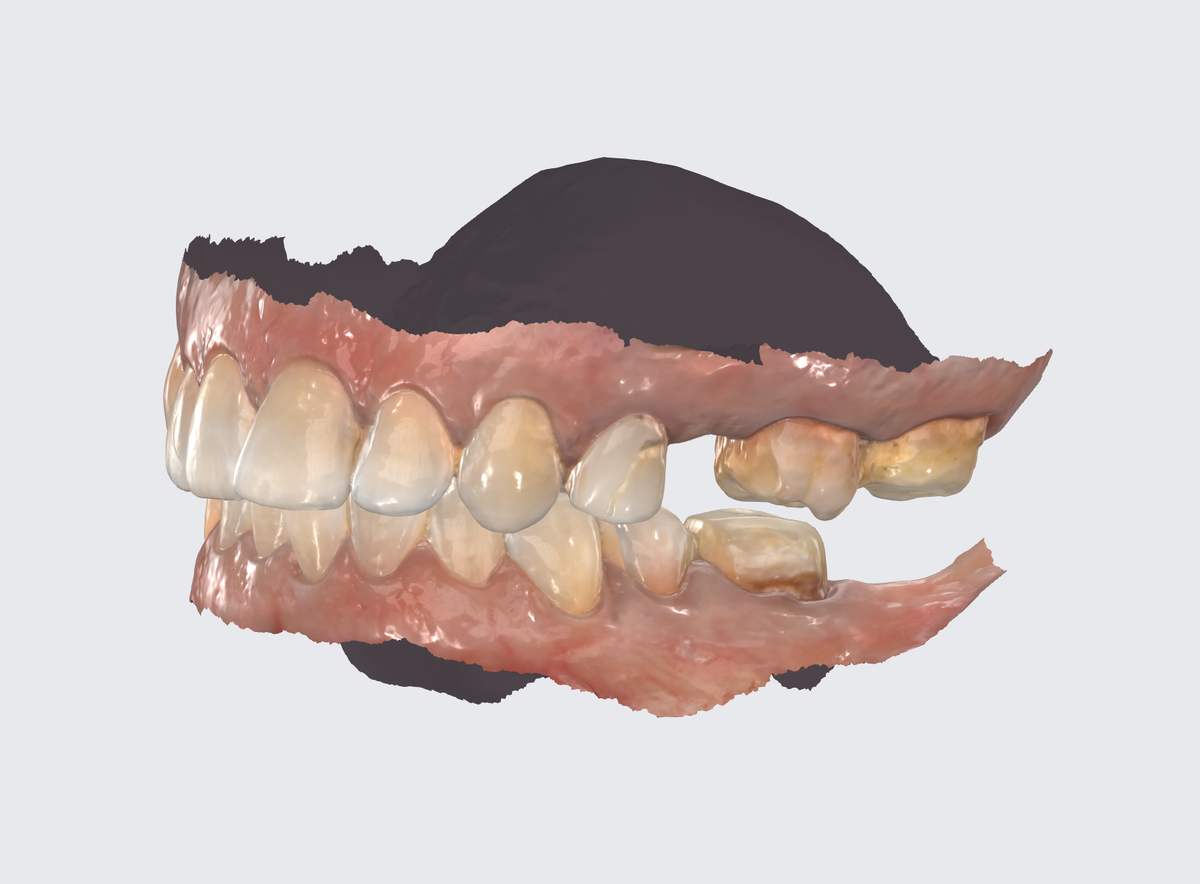

Через 2 месяца после установки временных коронок сканирование для коронок постоянных:

Все слепки цифровые. Сканируем, моделируем, фрезеруем.

При установке постоянных коронок (мост на импл антатах) во втором сегменте провели дополнительную пластику десны сразу - полноценная коррекция контуров:

Ткани будут заживать уже на постоянных коронках, приобретая максимально естественный вид.

Первый и четвёртый сегменты:

Вид жевательных поверхностей (листайте):

Было реализовано множество технических нюансов, которые не видны пациенту, но критически важны для долгосрочного успеха.